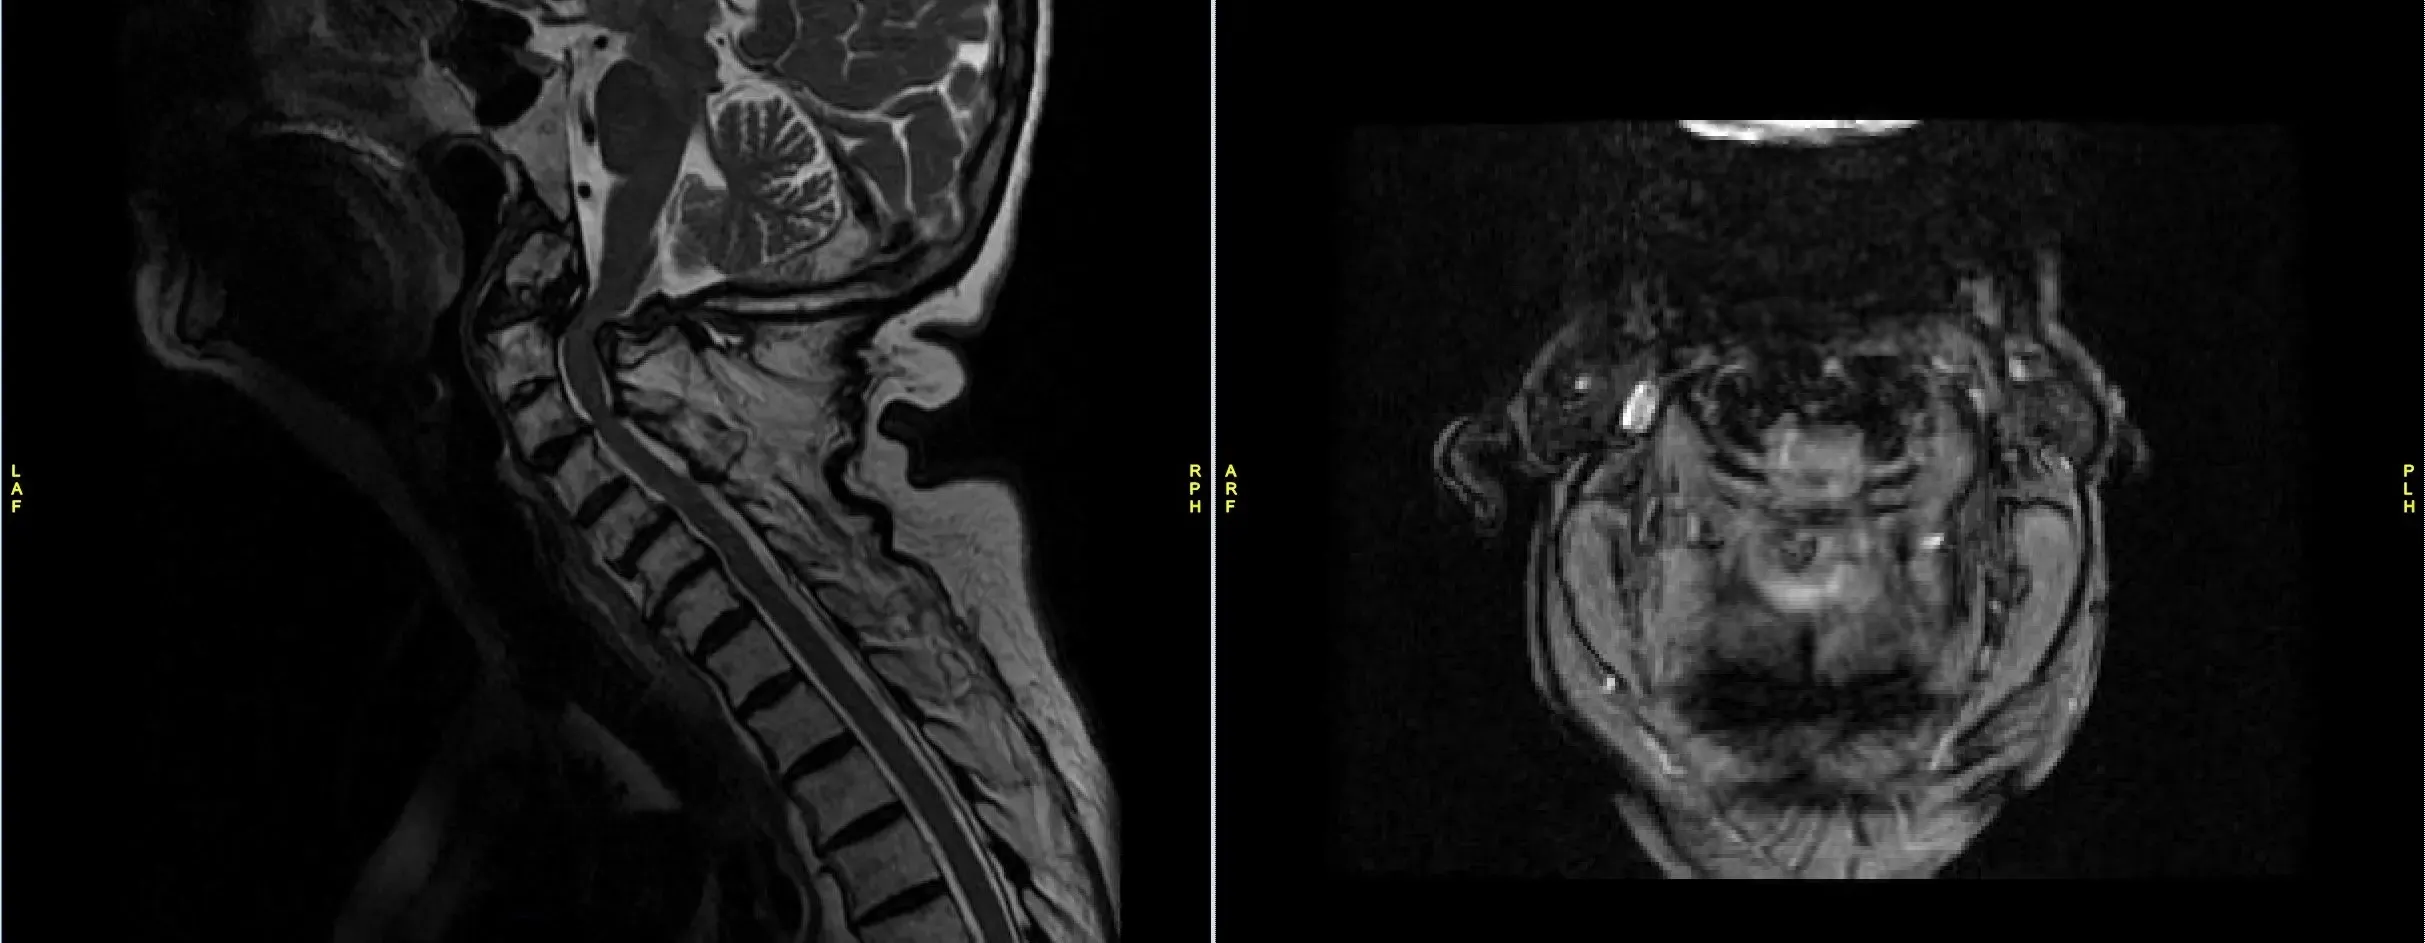

He was having balance issues along with weakness in all 4 extremities. X rays, CT scan and MRI showed a non-union of odontoid fracture with pannus formation and fibrous union, instability with compression of spinal cord at C1-2 level.